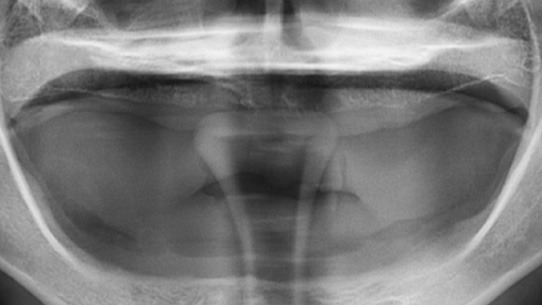

틀니가 번번히 탈락되어 일상생활이 불편하셔서 내원, 고정력이 없는 틀니를 사용하여 잇몸 염증과 통증 있으셨습니다. 상악의 경우 틀니를 오랫동안 착용하여 잇몸 뼈 소실이 심해 일반 틀니를 제작하고, 하악의 경우 임플란트 2개를 식립 후 임플란트 틀니를 제작해 드렸습니다.

상악은 잇몸뼈의 손실이 심한 상태